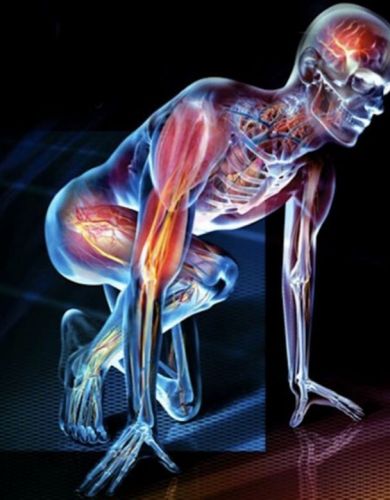

Physiology

Neuromuscular Physiology • Functional Anatomy